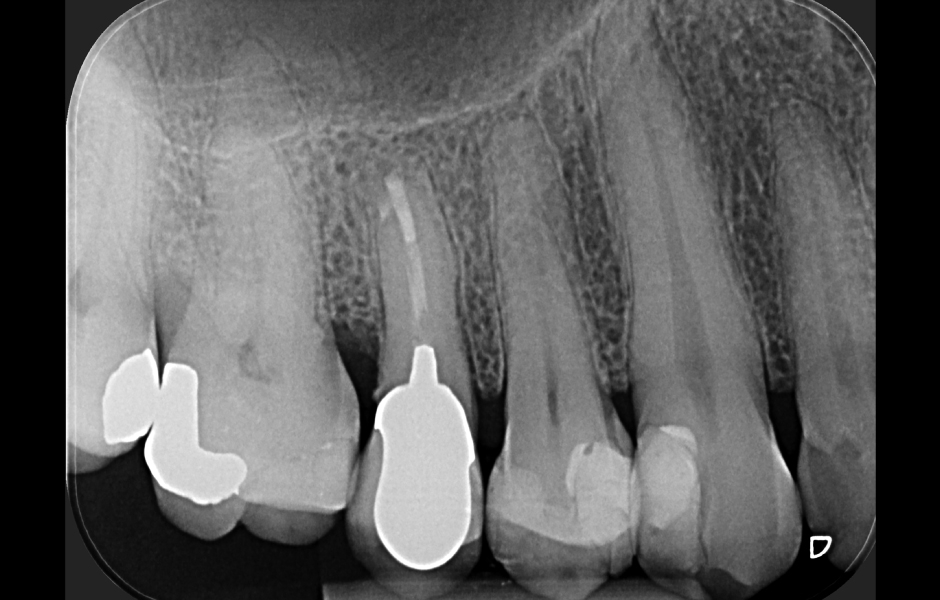

Obr. 2.1: Předoperační rentgenový snímek horního pravého druhého moláru. Je patrná drobná laterální radiolucence indikující přítomnost laterálního kanálku.